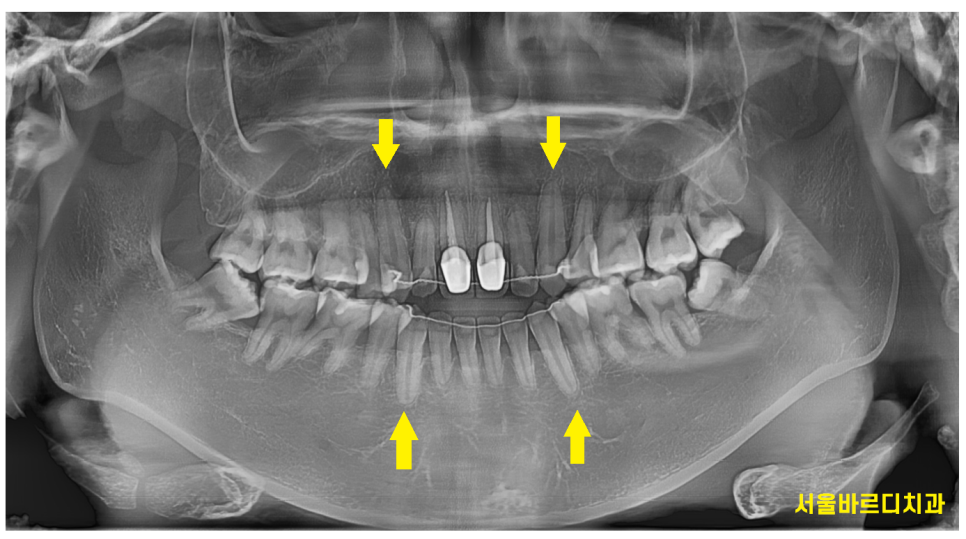

오실때마다 x ray 검사를 합니다.

과교정이 되고 있거나

치아 뿌리가 짧아지는듯 하면 교정력을 조정하면서

치아 뿌리를 최대한 보존하는데요.

그 이유는 치아 뿌리 길이가 길수록

치아 수명에 중요하기 때문입니다!

인체에서 송곳니가 뿌리가 가장 긴데

다른 치아들이 뽑힐 때에도 송곳니는 쉽게 뽑히지 않아요~~

(뿌리가 길어서 끝까지 생존하는 편이죠)

250103 길이가 가장 긴 송곳니